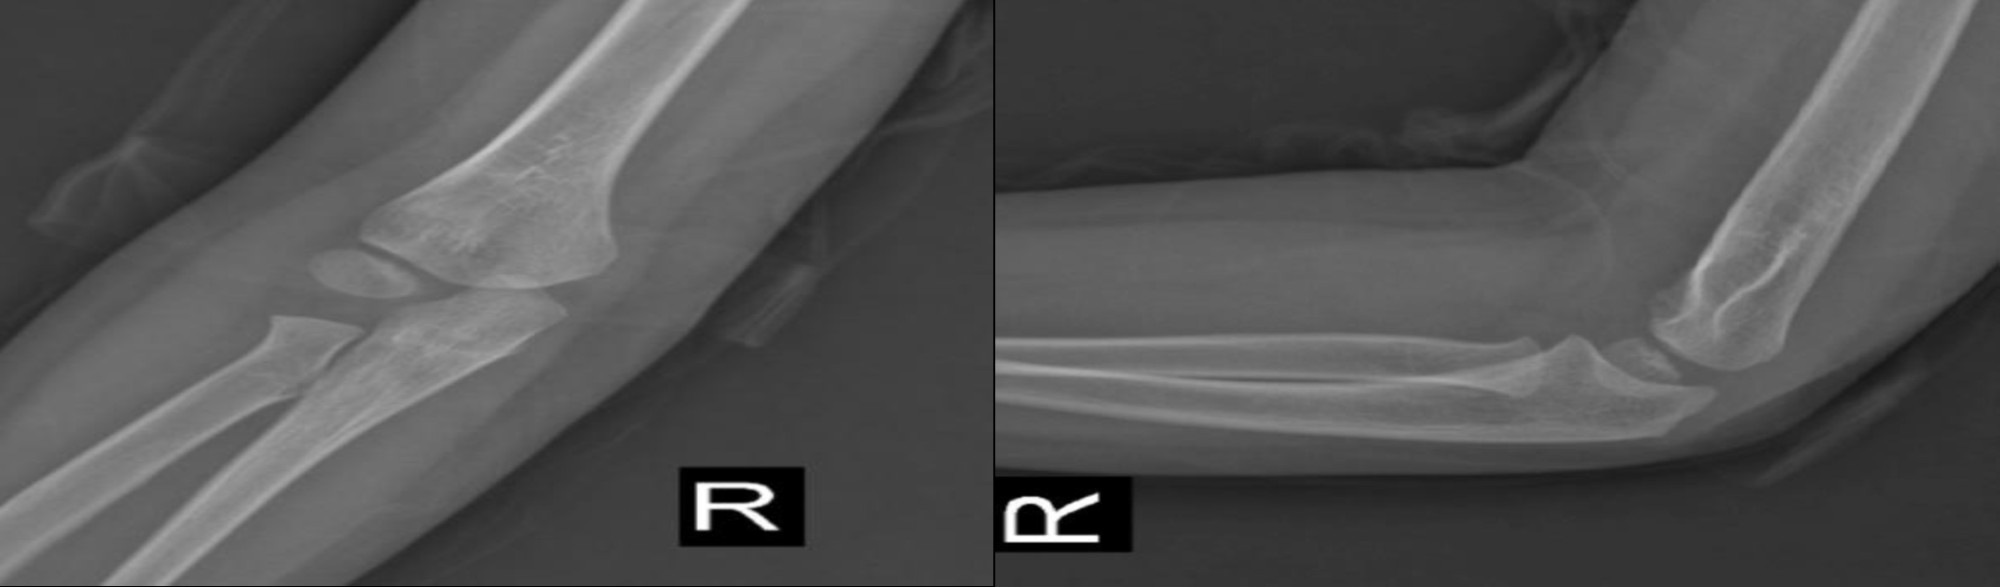

At follow-up three weeks later, the patient's splint was removed. The patient was revisited 50 days later, with radiographs indicating healing (Figure 3) and near-normal ROM despite mild varus (Figure 4). At 4-year follow-up, the patient was pain-free, with normal ROM (Figure 5) and radiographic evidence of complete remodeling (Figure 6), without physeal bar formation or deformity. Over the past four years, the patient has been able to perform daily activities without issues and has not required specific medical care. Notably, the mother later disclosed an unintentional injury by the father, not birth trauma, explaining the delayed referral. Informed consent was obtained for this report.

Figure 6. Radiographs at 4 Years with Complete Remodeling